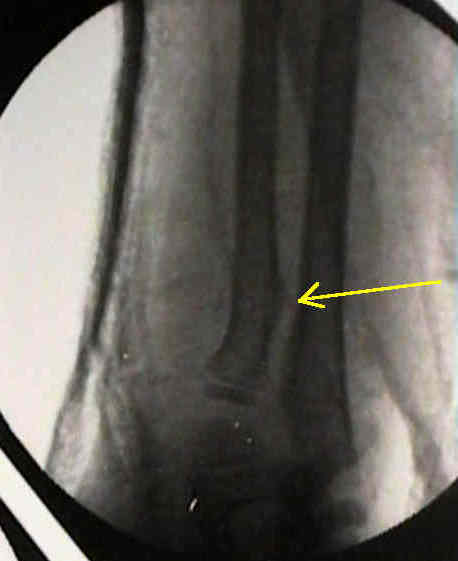

bayonette apposition

- generally bayonette opposition will require operative reduction (either closed with a Kapandji K wire levering technique or in some situations, an open reduction and fixation with K wires will be required);

- historically, overriding of a both bones forearm fracture was acceptable if...

- there was no deviation of radius and ulna toward each other;

- there was no encroachment of the interosseous space;